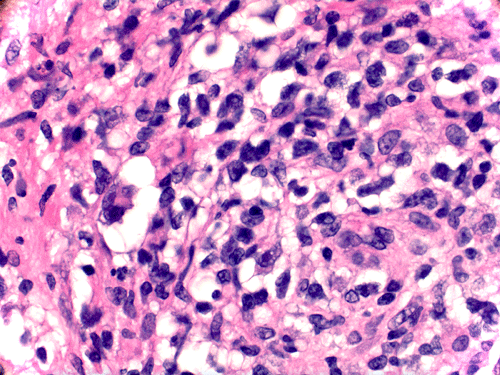

Histopathology: There is a necrotizing process with granulomatous reaction and perivascular lymphocytic infiltration. In some areas, there is concentric, perivascular lymphocytic infiltration surrounded by a granulomatous reaction (Panel A). On higher magnification, the lymphocytic infiltration appears to contain both small lymphocytes and scattered atypical cells with increased mitotic activity (Panel B and C). No definitive viral inclusion bodies are identified.

Special stains and Cultures: GMS stain, AFB stain, and immunohistochemistry for toxoplasma were negative. The large atypical cells were positive for CD20 (Panel D), and to a lesser extent CD30 and Epstein-Barr virus (EBV). Immunohistochemistry for CD68 highlighted numerous histiocytes, including those within vague granulomas. Numerous reactive T-cells were demonstrated by immunohistochemistry for CD45RO, CD2, CD3, CD5, CD7, and CD8, but not CD4.